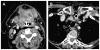

Cross-sectional imaging plays an important role in the evaluation of the retropharyngeal space (RPS) and the prevertebral space (PVS). Because of their deep location within the neck, lesions arising within these spaces are difficult, if not impossible, to evaluate on clinical examination. This article details the cross-sectional anatomy and imaging appearances of primary and secondary diseases involving the RPS and PVS, including metastasis and spread from adjacent spaces. The role of image-guided biopsy is also discussed.